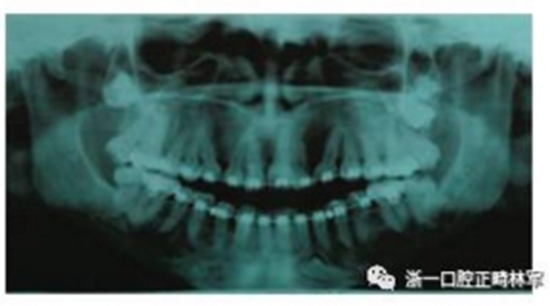

全景片示,上頜第三磨牙未萌,左上頜與左下頜各存在一顆多生牙。頭影測量數(shù)據(jù)如下。